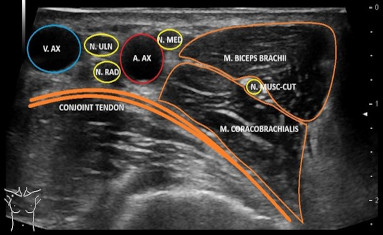

Nervi

Vandaag de dag is echografie van de zenuwen niet meer weg te denken binnen de musculo-skeletal ultrasound. Met de huidige apparatuur zijn de hoofdtakken en de aftakkingen van de zenuwen goed te visualiseren. Verdiep je in de anatomie en de landmarks om de zenuwen makkelijk te herkennen. Met deze kennis van de anatomie komt de pathologie vanzelf!